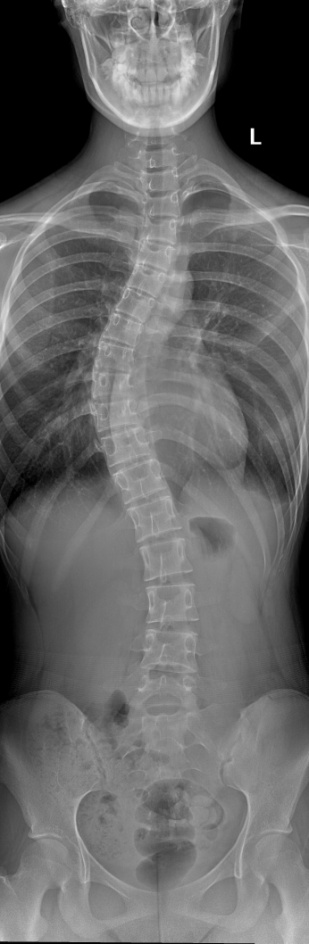

正常的脊柱从后面看应是一条直线,并且躯干两侧应该对称。当家长发现自己小孩有以下体态问题:如双肩不等高,肩胛骨 、胸廓不对称,臀部偏移,孩子向前弯腰时腰部左右不平,就要怀疑孩子是否有“脊柱侧弯”了。脊柱侧弯,也是脊柱侧凸的俗称。它是一种脊柱的三维畸形及序列异常。

全脊柱X线片,大部分是由脊柱分段拍摄,然后运用拼接技术拼接而成。

体位设计: 站立位摄影时患者站立于拼接架上,背靠支架,双手扶住扶手,双下肢直立,双足稍微分开,保持身体静止, 双眼平视前方; 站立侧位摄影时患者站立于拼接架上,身体一侧靠近支架面板; 同样是,双手扶住扶手,双下肢直立,双足稍微分开,保持身体静止;

脊柱侧弯的金标准是X光,所以如果真的担心自己有脊柱侧弯的话,通过拍摄全脊柱X线 片,就可以明确诊断了。